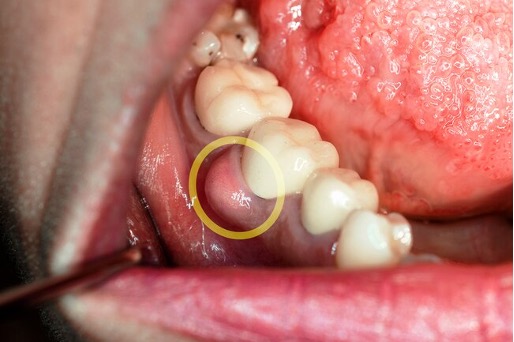

Pain from a gum disease abscess appears as pain and swelling on one side of the face. Patients often cannot pin-point them although they can point to the side of the face where the pain comes from. A gum abscess, occurs when a gum pocket becomes trapped with bacterial plaque or calculus and it cannot drain. There is increased temperature and the body releases enzymes and proteins to fight the infection. The result is pain, pus, swelling and bone loss. The underlying bone is destroyed and the tooth gets shaky. Treatment is usually antibiotics and/or drainage of the pus followed by prompt treatment by a periodontist or a dentist with experience in gum treatment. Abscesses, can cause a throbbing pain that may radiate to the jaw, face and neck.

Painful gum abscess associated with a gum infection